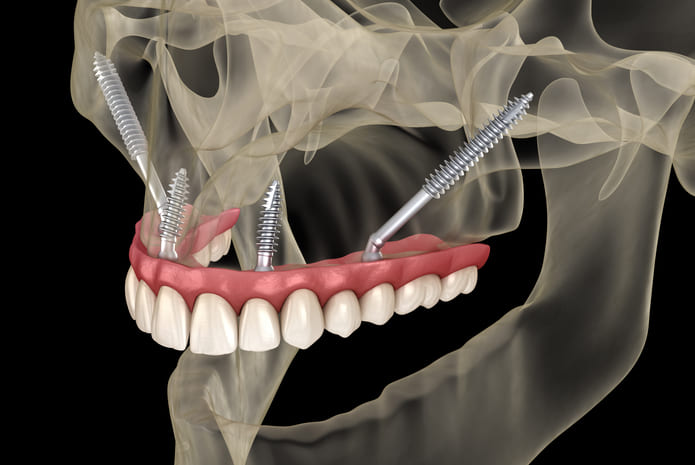

Los implantes pterigoideos son implantes dentales largos que se colocan en la apófisis pterigoidea , una zona ósea profunda y muy densa situada en la parte posterior del maxilar superior. Esta región ofrece una excelente estabilidad primaria , incluso en pacientes con gran pérdida ósea.

A diferencia de los implantes tradicionales, los implantes pterigoideos se colocan con una inclinación específica , anclándose en hueso de alta calidad y permitiendo la colocación de prótesis fijas sin necesidad de regeneración ósea previa.

No. Aunque suelen mencionarse juntos, implants pterigoideos y cigomáticos no son lo mismo , aunque ambos se utilizan en pacientes sin hueso.

Implantes pterigoideos : se anclan en la zona pterigoidea del maxilar

Implantes cigomáticos : se anclan en el hueso cigomático (pómulo)

En muchos tratamientos avanzados se combinan estas técnicas implantológicas para lograr una rehabilitación completa y estable sin injertos óseos.